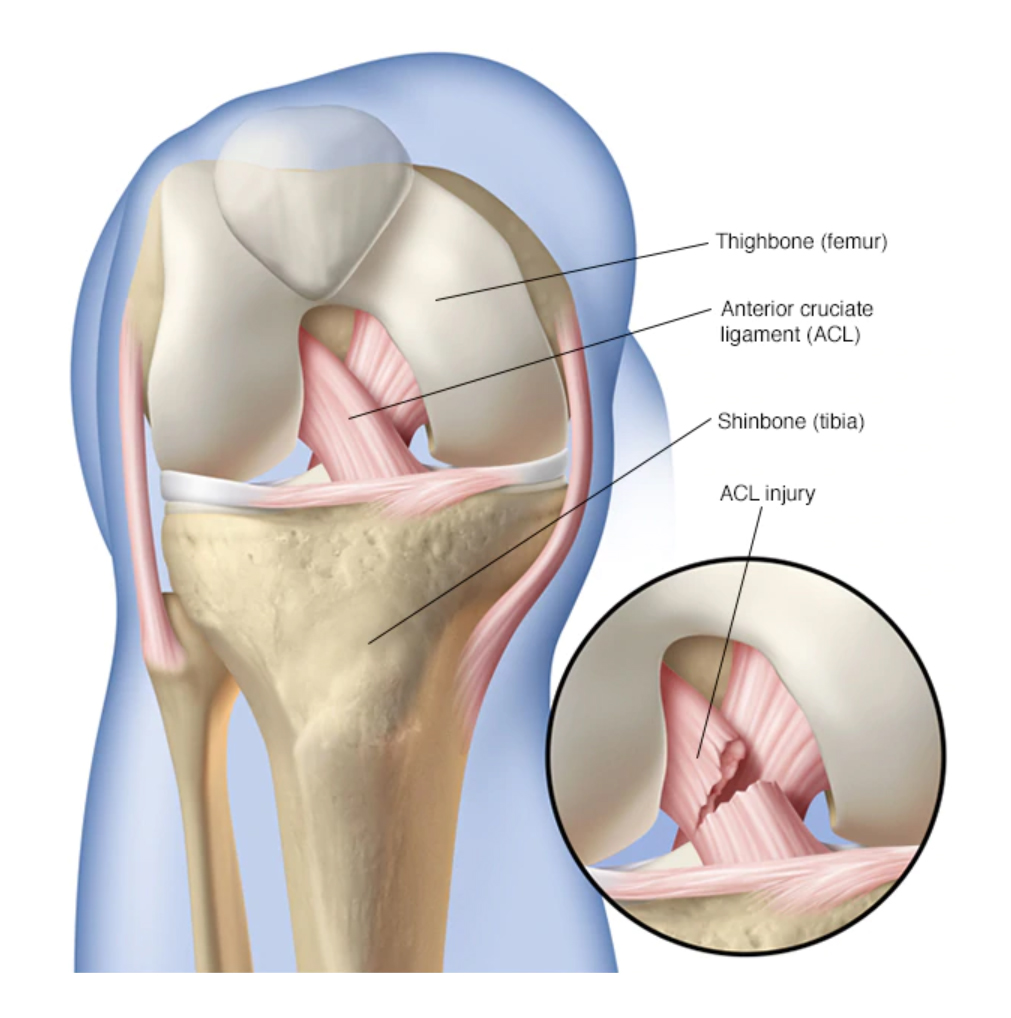

From the professional athlete to weekend warriors we strive in treating each athlete as if it were our own mother! Please visit our website at asmc.md for more information on what injuries we treat. Thank you! #medtwitter #sports #healthcare